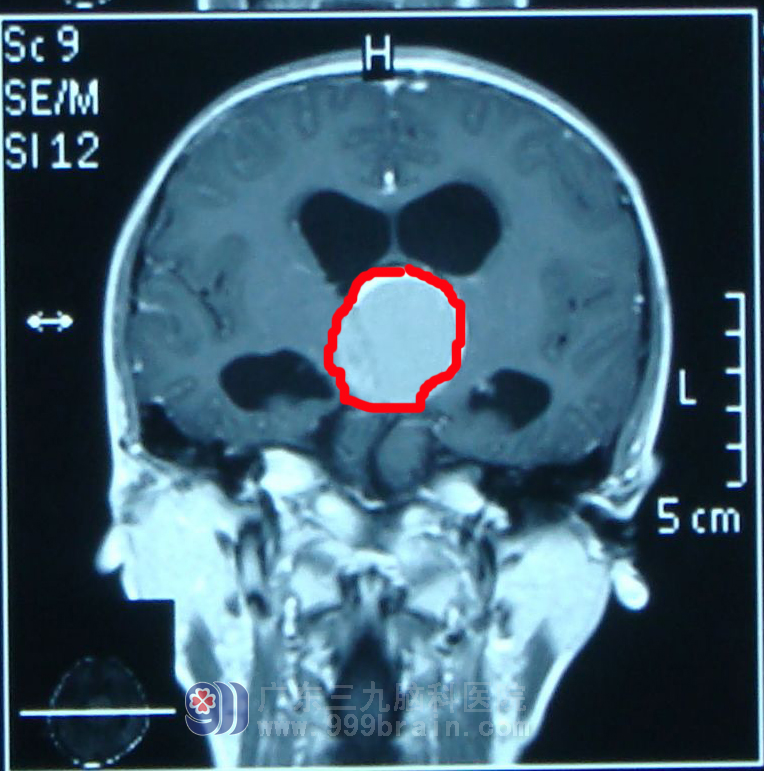

12岁的郭郭(化名)在1年前突然出现发作性头痛,在当地医院输液后症状得以缓解。一月前,郭郭头痛症状加重,经检查,发现鞍区肿瘤,肿瘤约3*3*6cm。由于手术危险性大,当地医院未能收治。多方打听之后,郭郭父母不远千里慕名将孩子送到了广东三九脑科医院小儿神经外科 。

进行了详细检查,完善相关检查后诊断:颅咽管瘤。

在做好充分术前准备、无手术禁忌症的情况下郭郭于2012-03-12在全麻下行“右侧翼点入路颅咽管瘤切除术”,术程进展顺利,显微镜下将肿瘤次全切,手术顺利。术后给予预防感染、神经营养、脱水、制酸、维持内环境等综合治疗。术后第二天复查头部CT及MRI示:颅咽管瘤切除术后改变。术后第九天切口拆线,愈合佳,I/甲。住院1个月,病情稳定,予出院。